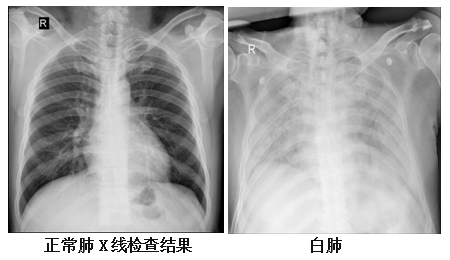

什么是白肺?发生白肺会有什么感觉和表现?如何早发现?一文说清

图片尺寸640x512